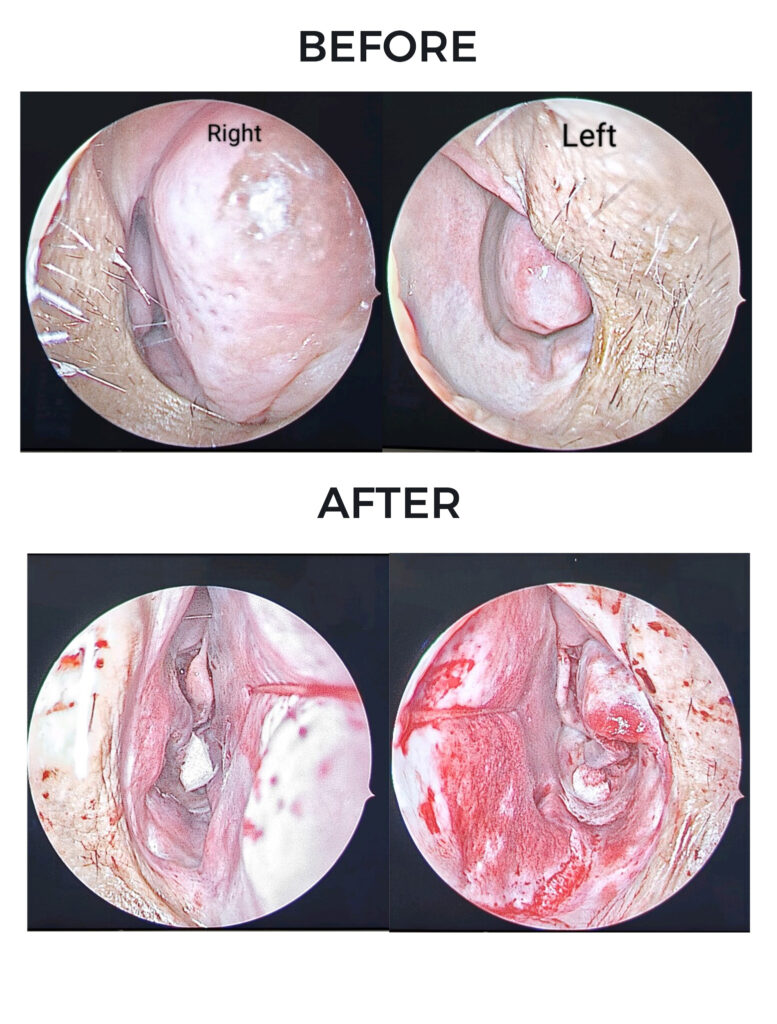

Whitish Cholesteatoma Flakes

Cholesteatoma of the Ear

Tympanomastoidectomy Surgery